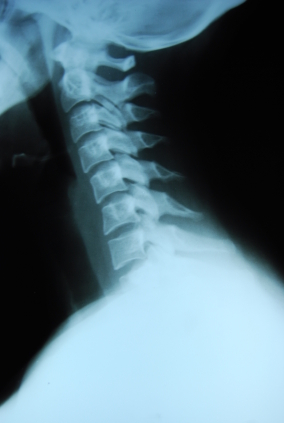

3. Spinal X-rays

The doctor will first determine if x-rays are necessary for your particular case. Spinal x-rays reveal how an individual spine deviates from normal alignment.

The above x-ray is that of a neck or cervical spine from the side, with the patient facing left. You can see that the neck appears straight. The cervical spine, however, should have a forward curve. Only an x-ray can reveal the precise spinal displacements.